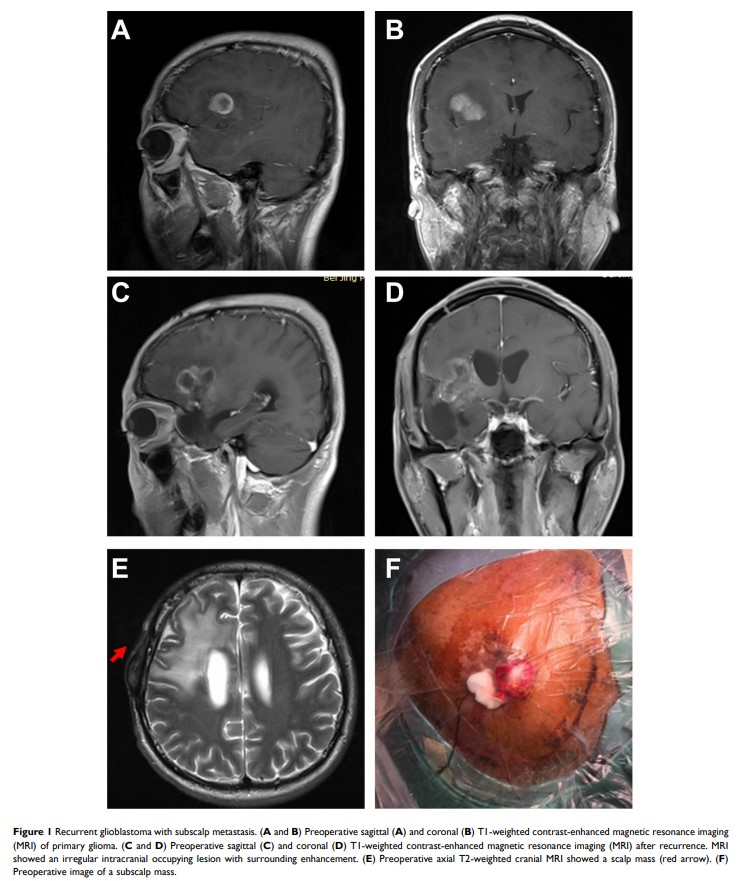

颅内胶质细胞瘤头皮下复发的生物学特性和治疗方法